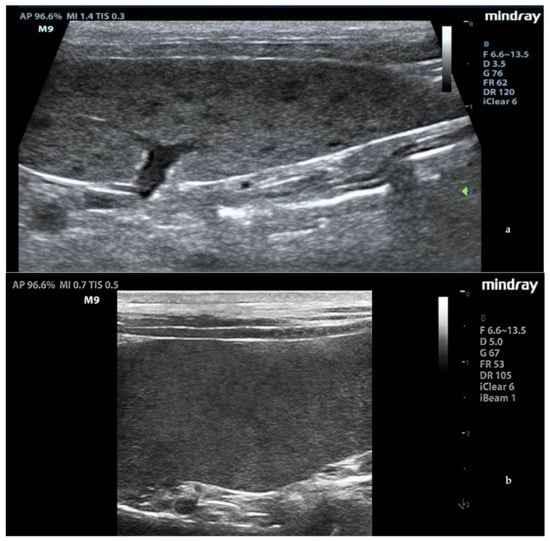

3.3. CEUS

In leishmaniotic dogs without splenic changes detectable from ultrasound examination and control dogs, CEUS exams showed the normal rapid enhancement of splenic arteries (10–13 s) and a heterogeneous phase of the enhancement of splenic tissue that became homogeneous at the end of wash-in with a slow decay (Figure 3).

Figure 3.

Normal spleen images acquired during CEUS (contrast-enhanced ultrasonography) exam. (a) Enhancement of the splenic arteries at 8 s after contrast injection; (b) beginning of heterogeneous phase of enhancement 10 s after contrast injection; (c) homogeneous enhancement at 60 s after contrast injection. F: probe’s frequencies; D: distance; G: gain; FR: frame rate; DR: dynamic range; AP: acoustic power; MI: mechanichal index; TIS: tissue imaging specific; M9: ultrasound system; T: tissue; C: contrast. Green arrows: focal points.

Enhancement in the moth-eaten parenchymas had a heterogeneous distribution pattern with hypoenhancement/no enhancement areas in both the wash-in and wash-out phases; in marbled spleens, enhancement intensity was weak and heterogeneous (Figure 4 and Figure 5).

Figure 5.

CEUS images at the end of the wash-in phase in (a) moth-eaten, (b) marbled (heterogeneous enhancement), and (c) normal (homogeneous enhancement) spleens. F: probe’s frequencies; D: distance; G: gain; FR: frame rate; DR: dynamic range; AP: acoustic power; MI: mechanichal index; TIS: tissue imaging specific; M9: ultrasound system; T: tissue; C: contrast. Green arrows: focal points.

CPD examination and CEUS were used to study splenic microvascularization. After the inoculation of the contrast agent, normal splenic parenchyma showed the rapid enhancement of the small splenic arteries, a heterogeneous phase of enhancement that became homogeneous at the end of the wash-in phase, and a slow wash-out [39]. Though the contrast medium did not have a late tissue phase in the dog’s spleen, the slow decay of enhancement would have been related to the accumulation in the sinusoids network [40]. A CPD examination showed no flow signal from small hypoechoic areas in the moth-eaten pattern of the spleens. In moth-eaten spleens, CEUS was used for the first time and showed, through a persistence of diffuse inhomogeneity with areas of hypoenhancement or absence of enhancement, that the alterations found in the B-mode images also led to a modification of the vascular architecture throughout the organ. A similar heterogeneous appearance and a widespread hypoenhancement were also found in the marbled spleens. Spleen microvascular architecture changes emerged in L. infantum-positive dogs from an ultrastructural study independently of their antibody titers. A marked scarcity of the sinusoidal system sheet that surrounds the central artery/arteriole of the white pulp, a huge development of pulp venules and veins, and the presence of a development of reticular fibers were reported [13]. Interestingly, we evidenced that an abnormal pattern of enhancement was only in spleens with B-mode ultrasonography alterations, and we can only speculate about these results. This in vivo study of vascular architecture obtained with CEUS was, however, not able to highlight changes in the splenic vascular pattern in all infected dogs other than what was reported with ultrastructural evaluation [13]. The statistical analysis of the CEUS quantitative parameters, relating to the speed and volume of splenic blood flow, did not show statistically significant differences in the examined ROIs. This was probably due to the inhomogeneity of splenic enhancement in leishmaniotic subjects that was not quantitatively detectable through the pixel analysis of different areas, even when comparing relatively small ROIs, because of the widespread alteration of the splenic vascularity of parenchyma. Substantial evidence supports that the spleen plays a key role in the immunopathology of VBP infections [41,42]. Splenomegaly might be due to a multiplication of organisms within circulating mononuclear cells and mononuclear phagocytic tissues of spleen and lymph nodes. Splenomegaly is a result of reactive lymphoid hyperplasia and concurrent extramedullary hematopoiesis [43]. In canine babesiosis and ehrlichiosis, the most common splenic ultrasonographic findings have been a diffuse heterogeneous hypoechoic pattern and generalized splenomegaly [44,45]. CEUS exams were performed in the spleens of dogs with subclinical ehrlichiosis, and a higher velocity of blood flow (lower wash-in time, peak enhancement time, and wash-out time) compared to data from healthy dogs examined in previous studies was seen [45]. In our study, molecular investigations of blood samples and splenic aspirates showed them to be negative for R. conorii, B. canis, E. canis, A. phagocytophilum, A. platys, and C. burnetii, so we can consider it unlikely that the ultrasound changes of the spleen could be traced to other VBP coinfections with L. infantum.